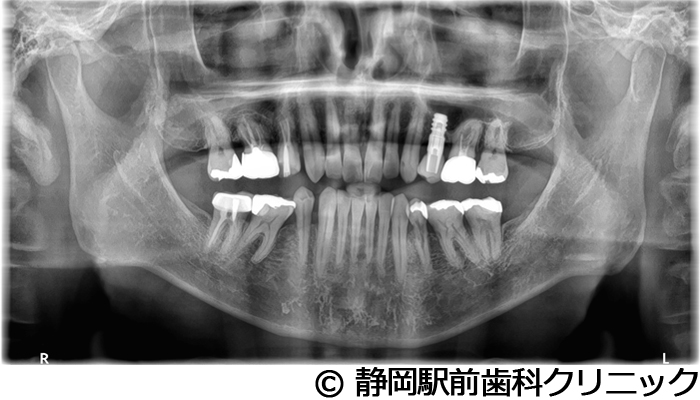

【症例5】全顎的インプラントとセラミックによる審美補綴

- 治療前

- 治療後

- 治療名

- 全顎的インプラントとセラミックによる審美補綴

- 費用

- 1,800,000円(税込)

- 期間

- 1年6ヵ月

治療内容

-

患者様の症状

全体的に歯がないため、噛めない。インプラント治療希望。

治療方法

全体的に残根は抜歯を行い、術前にCTを撮影し緻密に治療計画を立てた。インプラント埋入はブロックごとに行い、噛み合わせの調整を重ねた後、人工歯を被せて咬合と審美の回復を行いました。

治療結果

しっかり奥歯で食べ物を噛み切ることができるようになり、何でも食べることができるようになったと喜んでいただくことができました。口元を気にせずに笑うこともできるようになり、見た目もキレイになったとご満足いただけました。

※治療結果は個人差があります。

治療を行う上での注意点(リスク・副作用)

術後は、出血、腫れ、痛みなどが出る可能性があります。